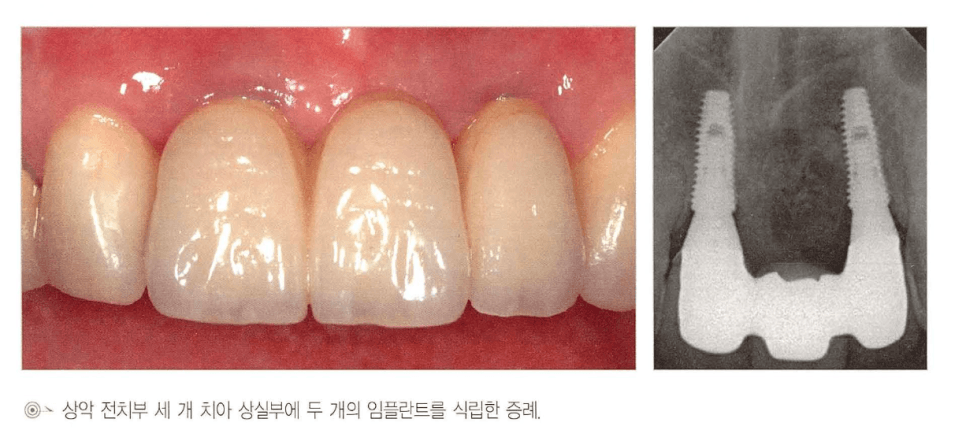

상악 전치부 2~3개 상실

[그림 3] 상악 전치부 3개 상실에서 임플란트 2개 + 중간 pontic으로 완성한 실제 임상 증례(구강 내 사진과 방사선 사진). 치간 유두와 잇몸 형태가 자연스럽게 유지되는 것을 확인할 수 있습니다.

- 전치부 2개 상실 — 임플란트 간 거리 2.5~3mm 이상 확보가 어려운 경우, 임플란트 1개 + 캔틸레버 설계가 심미에 더 유리할 수 있습니다.

- 전치부 3개 상실 — 임플란트 3개를 나란히 심으면 치간 유두 소실과 “black triangle”이 생기기 쉽습니다. 임플란트 2개 + 1 pontic이 통상 우수한 결과를 보입니다.